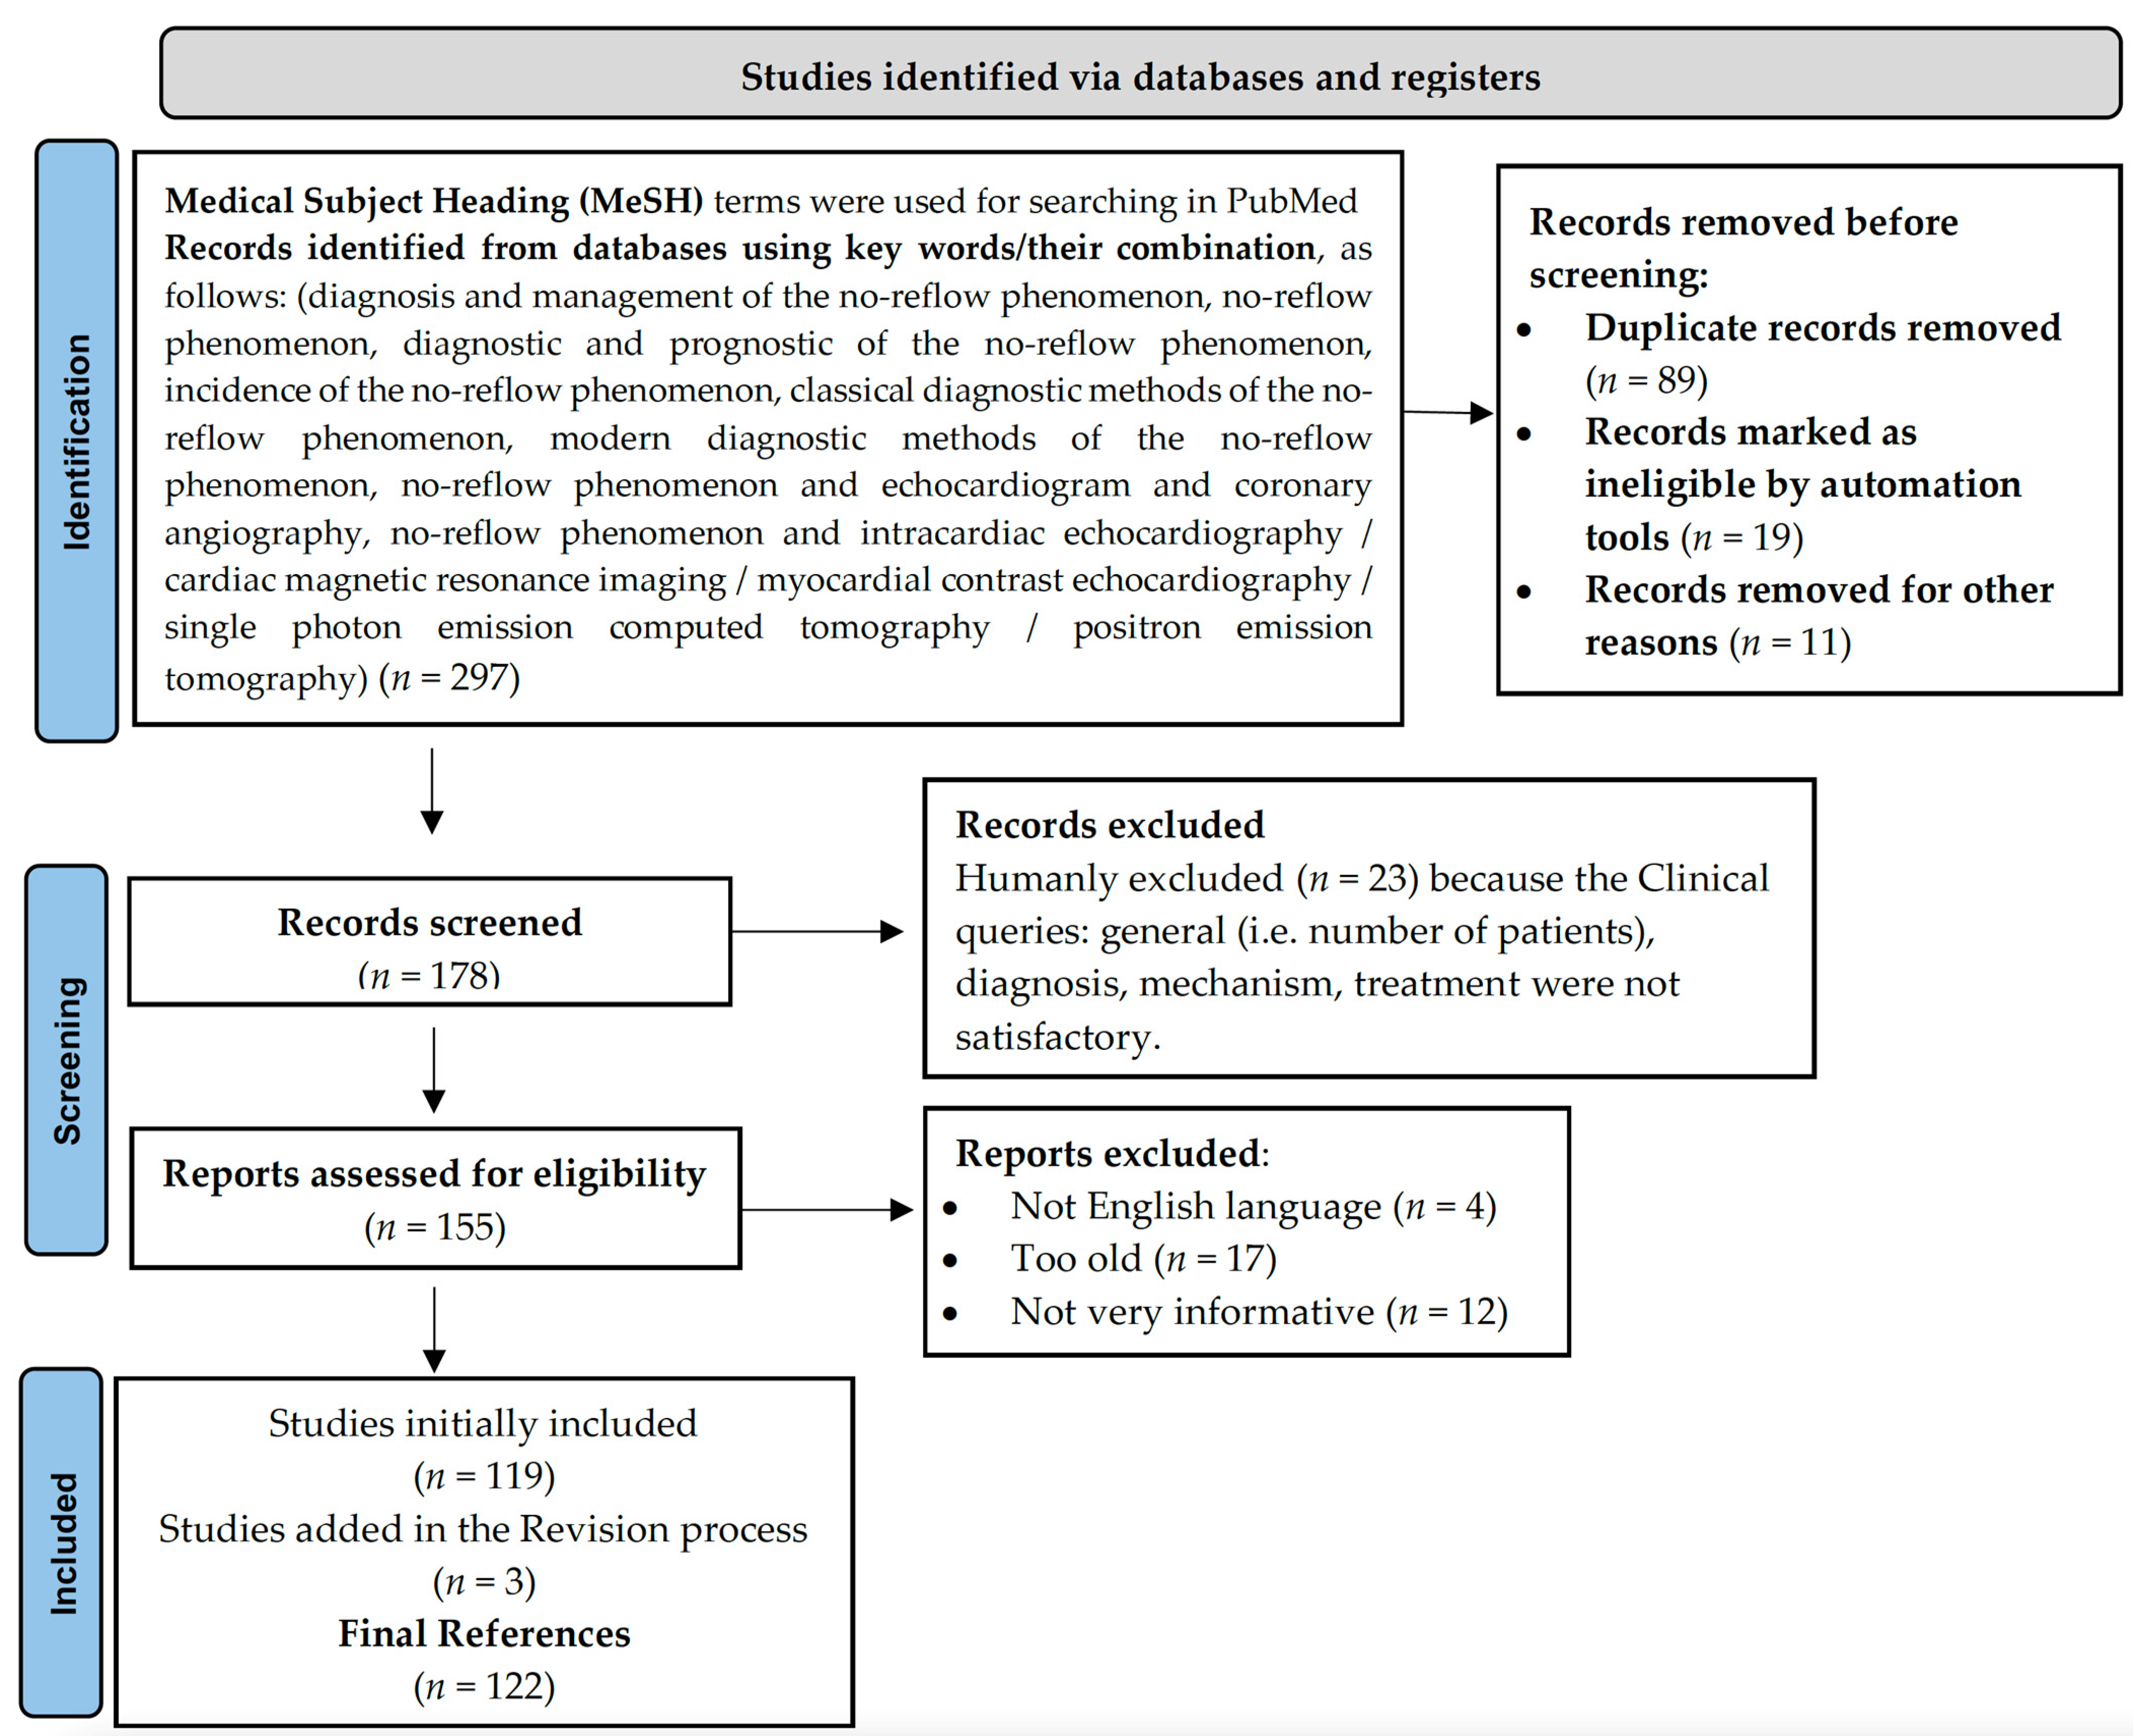

2. Methods